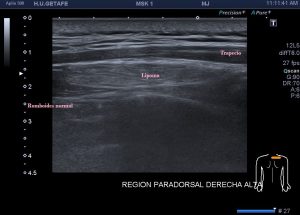

Los vientres anteriores de los músculos Digástricos, que son el objeto del desarrollo de este Post, son dos estructuras musculares redondeadas en el corte transversal, imagen 1, y alargados si los estudiamos en el eje largo, imagen 3, mira:

Ecográficamente los músculos digástricos en eje corto tienen semiología hipoecogénica, en aspecto de noche estrellada, como la de hoy, y en el eje largo en forma de penacho o en forma de plumas con las fibras alargadas y paralelas a la superficie.